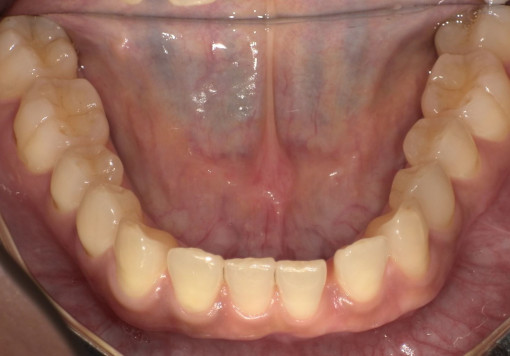

- 主訴:前歯のガタつき・上下の歯並びの不均一を改善したい。

根管治療途中の歯を治したい - 治療内容:マウスピース型矯正装置(SureSmile)による全顎矯正。

下顎1本インプラント埋入 - 治療期間:約36ヶ月

- 診断結果:

・上下顎に叢生を認め、特に上顎前歯部の位置不良が強い状態。

・噛み合わせのズレがあり、審美性・機能性の改善が必要と判断。

・抜歯を伴わないマウスピース矯正での改善が可能と診断。

歯根破折 - 治療後経過:

・前歯部の配列が整い、正中・噛み合わせが改善。経過も良好。 - 治療費用:マウスピース矯正(SureSmile):88万円税込

インプラント45万円税込

※症例により費用は前後します。

リスク・副作用:

・歯の動きに伴う痛み・違和感が数日出ることがあります。

・装着時間が不十分な場合、計画通りに歯が動かないことがあります。

・矯正後に保定装置を適切に使用しないと後戻りの可能性があります。

・虫歯・歯周病がある場合、先に治療が必要となる場合があります。